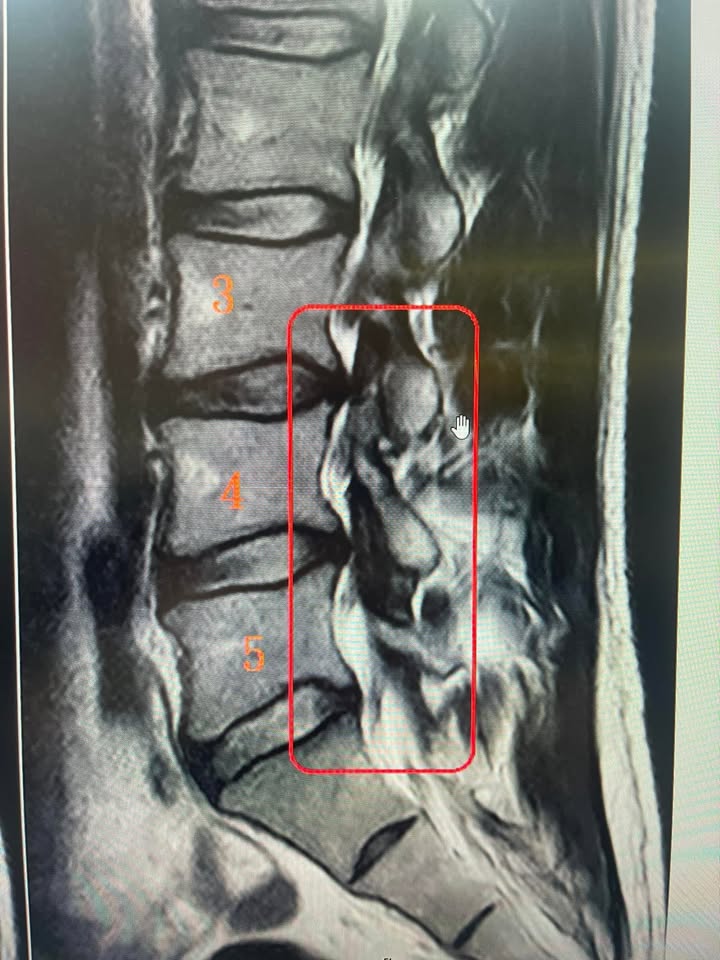

Cervical Spine Treatment Cases 精彩回顧 開業這麼久,第一次收到這種很奇怪的評論。 就三個字「說診所服務態度差」,真的非常 ... 2023.03.30 感謝台灣針刀醫學會對小弟的肯定👍 很榮幸受邀擔任專科醫學會理事任務❤️ 一步一腳印讓... 2023.03.21 MONZA SP3限量馬王樂高 患者花超過一百個小時組裝而且全車改裝LED 收到這種禮物差點哭... 2023.02.11 「是誰的心啊 孤單地留下,他還好嗎 我多想愛他,拿永恆的淚 凝固的一句話,也許可能... 2023.02.02 😊立澄復健科洪辰宇院長親自贈送金門高粱 🈵脊椎針刀專科跨界合作復健科大師 2023.01.19 ❤️穿越十八小時的國際航班 💟俄羅斯華人工程師一下飛機立刻診所報到 ❇️脊椎整合中醫微... 2023.01.04 2023年的第一天上班日,傍晚下班時拿著患者訂製的雷射雕刻威士忌酒杯,希望所有患者平... 2023.01.03 ⭕️值得喝采的一天👍。 ⭕️七週治療椎間盤明顯吸收回去。 ❗️當初走路5分鐘就開始大痛。 ... 2022.10.08 特別且有重要意義的禮物。 今天早上收到感覺很榮幸。 2022.12.30 🌀超級大驚喜! ⚠️椎間盤巨大突出患者突然拿AirJORDAN 第一代的復刻鞋說要送給徐醫師 ... 2022.11.18 前言:這是一個非常特殊且難度很高的案例,我們治療了十週,將近兩個半月的治療,患者... 2022.11.08 原來腰椎針刀是一件開心愉快的事情。 愉快的週末,從快樂屠龍刀開始。 你快樂,所以我... 2022.11.05 #耳鳴眩暈有可能是頸椎問題 #24小時處於手麻手痛的狀態 #眩暈加速惡化造成生活上的... 2022.11.16 每次患者叫的亂七八糟的時候,這首神歌突然出現在我腦海中,今天還忍不住唱出來,還被... 2022.09.23 花蓮針友粉絲林董犒賞醫療團隊,整箱十台斤起跳,分成好幾袋贈送每個護士跟徐醫師,人... 2022.09.14 ← 上一頁 1 2 3 4 5 下一頁 →